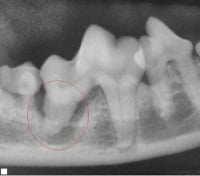

Dental abscess

Source: Tieton Drive Animal Clinic